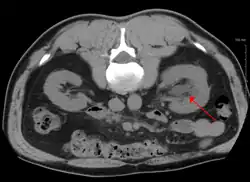

CT scan of bilateral hydronephrosis due to a bladder cancer